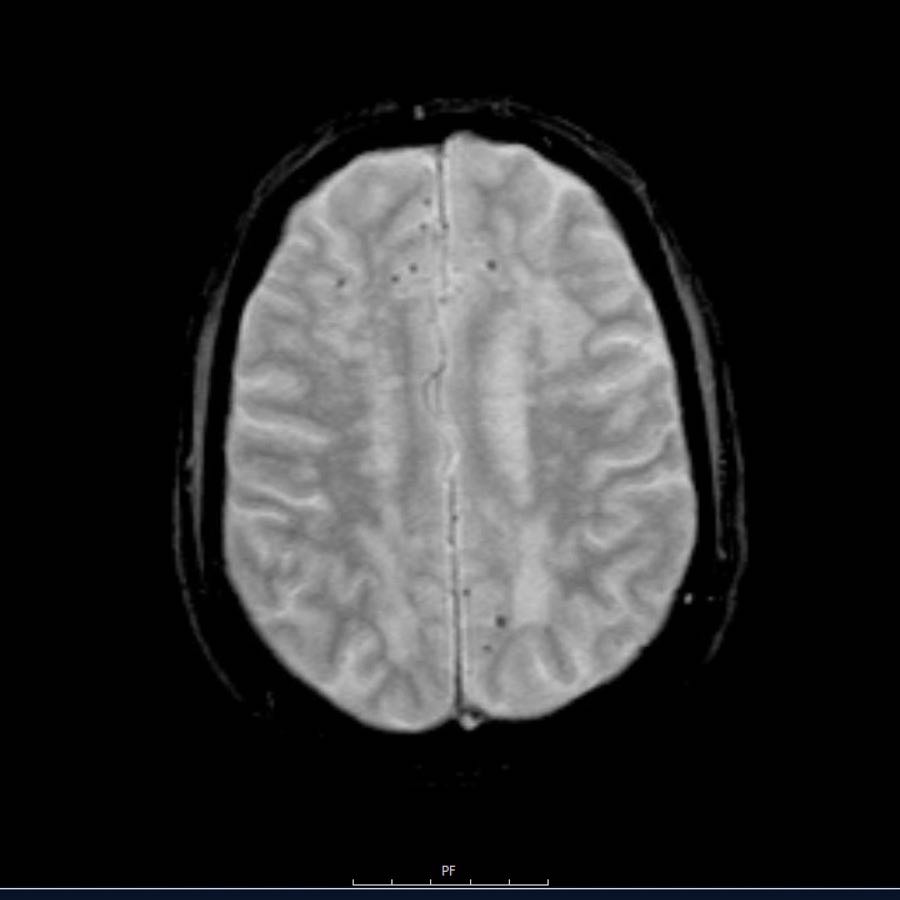

Các ổ xuất huyết nhỏ này còn được gọi là xuất huyết vi thể (microbleeds).

Lưu ý số lượng rất nhiều các ổ xuất huyết nhỏ này, phân bố chủ yếu ở vùng ngoại vi của não.